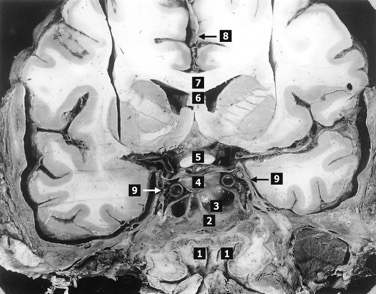

Фото 2. Г. Ф. Добровольский объясняет особенности строения головного мозга

Фото 3. Представленные в докладе препараты уникальны, изготовлены автором с помощью учеников, с применением сложных методов фиксации ткани и диссекции ткани мозга, наливки сосудов разноцветным силиконом.